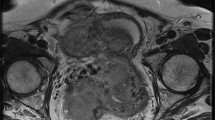

Tubo-ovarian abscess in a 14-year-old woman. (a) Axial and (b) sagittal T2-weighted images show heterogeneous, multilocular mass, with hypointense internal incomplete plicae and high to intermediate signal intensity fluid content (white arrows) in the pelvic cul-de-sac. (c) On sagittal fat-suppressed T1-weighted images, the mass’ content shows low signal intensity (white arrows). (d) Axial DW image (b = 800 s/mm2) and (e) corresponding ADC map show that the lesion’s content demonstrates restricted diffusion with high signal intensity (white arrow) on DWI image and low signal intensity (white arrow) on ADC map, a finding consistent with a purulent content. (f) The presence of primary ovarian follicles demonstrated the ovarian nature of the lesion (H&E 200X)